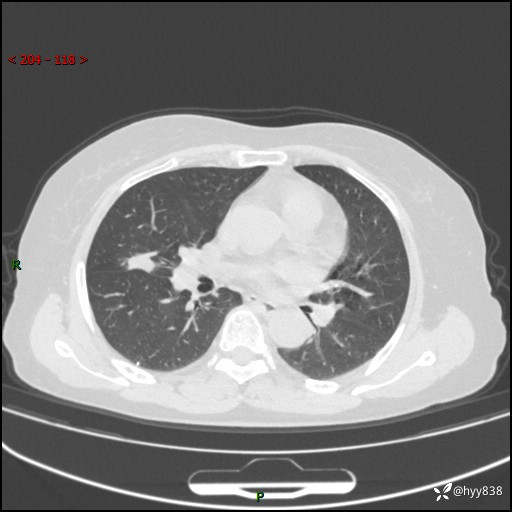

现病史:患者1月前无明显诱因出现痰中带鲜红色血丝,伴间断咳嗽,晨起明显,无胸闷、胸痛,无恶心、呕吐,无发热、畏寒,无活动后气短,无盗汗、咯血、消瘦等不适,未行诊疗。患者1天前于我院就诊,行胸部CT:右肺中叶及右肺下叶结节影,右肺上叶磨玻璃影,左肺上叶纤维灶。门诊以“咯血原因待查 肺结节”收入我科。 起病以来,患者精神、饮食、睡眠尚可,大小便正常,体力、体重未见明显改变。

胸部CT平扫+增强